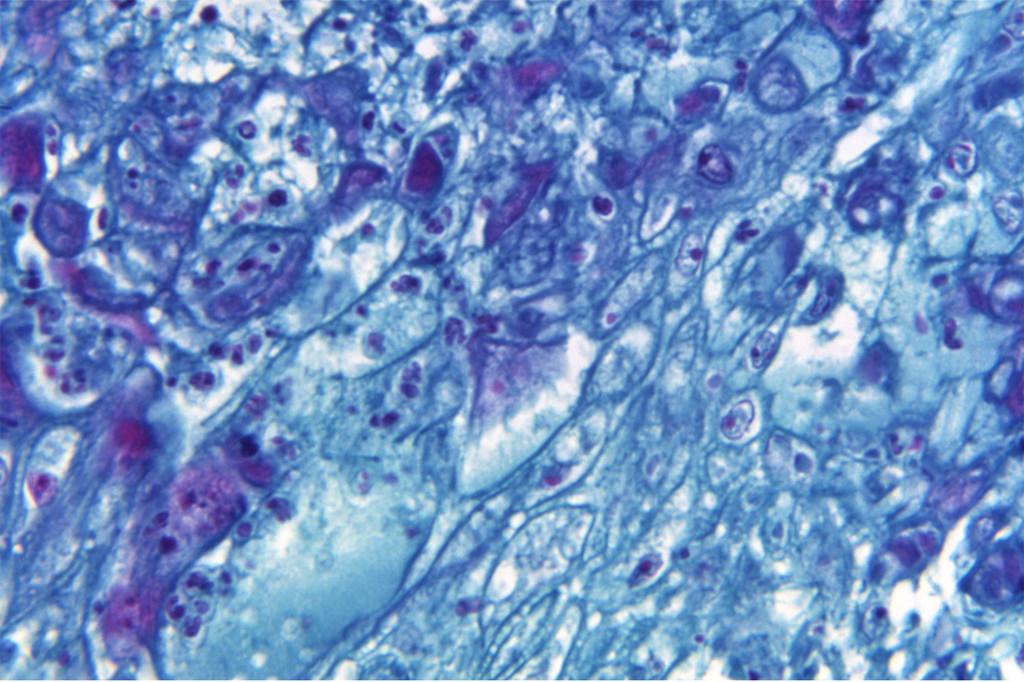

La viruela del mono es, en general, una enfermedad que no pone en peligro la vida de las personas sanas. La enfermedad es más conocida en los países africanos, donde se ha observado durante décadas, y donde se han registrado ocasionalmente muertes, cinco en lo que va de año, incluso en niños y ancianos, así como en personas con enfermedades subyacentes.

No obstante, la viruela del mono puede causar una serie de signos y síntomas, como dolorosas llagas. Algunas personas que desarrollan síntomas graves pueden necesitar atención en los centros de salud. Entre las personas con mayor riesgo de padecer una enfermedad grave o complicaciones se encuentran las mujeres embarazadas, los niños y las personas inmunodeprimidas.